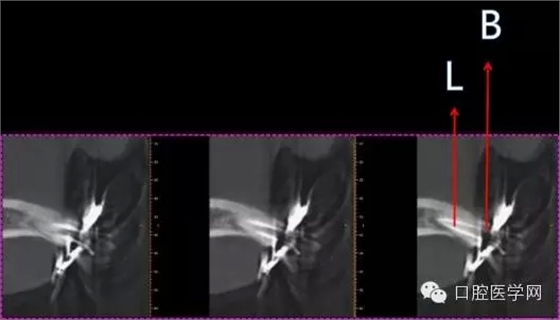

B=14mm

L=18mm

根管長度定位

根尖到位